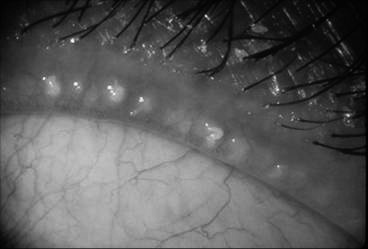

• Imaging the lid margins - Detects Demodex, Blepharitis and Ocular Rosacea.

Demodex

Demodex are tiny mites that commonly reside in our hair follicles and sebaceous glands.

The cause of chronic blepharitis can sometimes be secondary to a Demodex infestation of the eyelid follicles. Your optometrist will be able tell by examining your eyelashes if there is an overpopulation of the demodex mites.